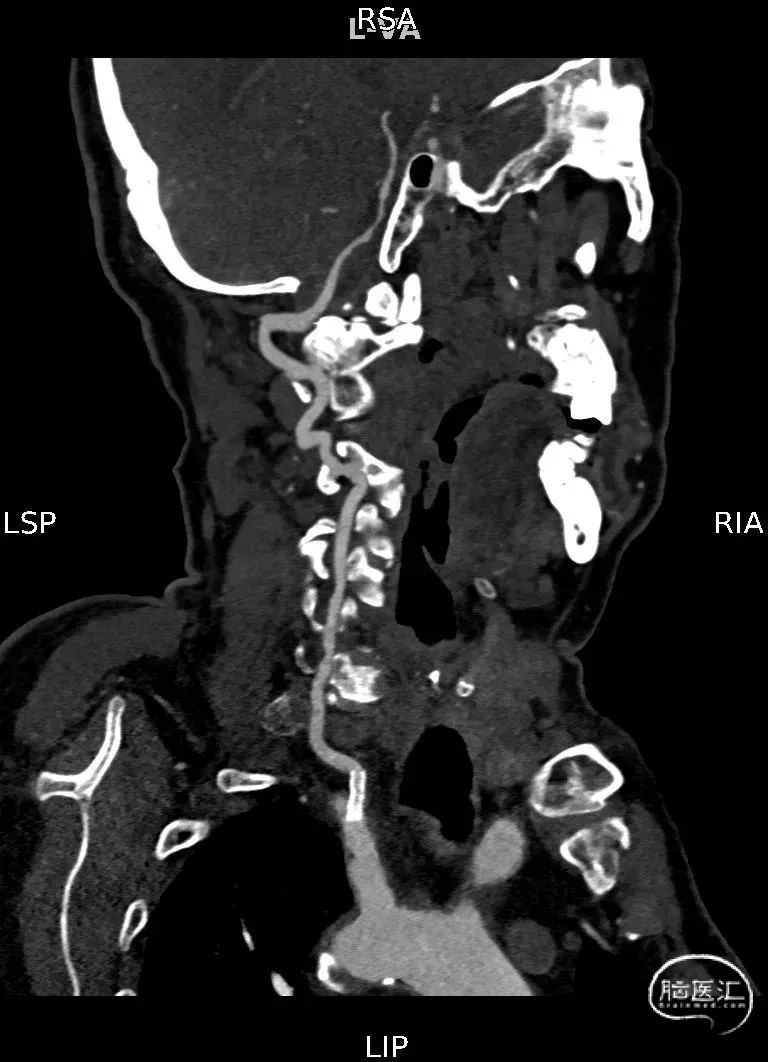

CTA提示:右侧椎动脉纤细,左侧椎动脉V1、V4段纤细。

术前DSA影像

右侧颈内动脉起始部中度狭窄,未见血流向后循环代偿。

左侧颈内动脉造影提示后交通开放,代偿供应后循环。

左侧椎动脉开口重度狭窄,前向血流缓慢,V4闭塞。